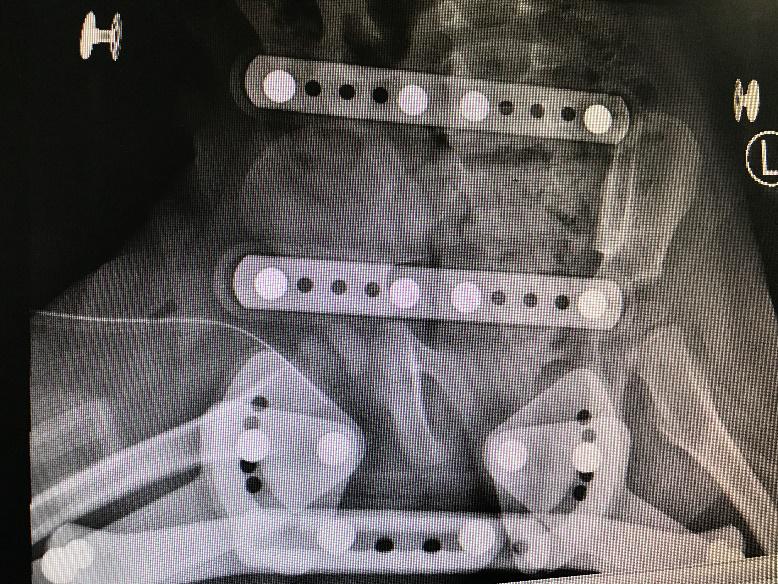

病理性髋关节脱位发生率高,达81.8%(9/11)。其中6例(54.6%)患儿入院时已有病理性髋关节脱位或半脱位情况,1例为高位脱位;3例患儿治疗过程中出现病理性髋关节脱位或半脱位。5例病髋患儿经一次手术脓肿切排冲洗引流、抗感染及人类位支具固定治疗后髋关节复位(脓肿切排时予检查髋关节复位及稳定情况从而判断是否使用支具);1例行手术切开复位后石膏固定维持复位;1例MRSA感染患儿经4次手术脓肿切排冲洗引流及支具治疗后髋关节复位;1例MSSA感染患儿入院时已有高位脱位,经清创冲洗引流后感染控制,但仍遗留高位脱位情况,以后需要进一步行重建手术治疗;1例目前有残存髋关节半脱位。36.4%放射学预后满意,63.6%(7/11)放射学预后不满意,18.2%(2/11)有残留畸形需要行重建手术。11例患儿的一般情况见表 1。病理性髋关节脱位后支具治疗见图 5。

| 图 5 治疗过程中出现髋脱位,人类位支具固定,提示复位 |